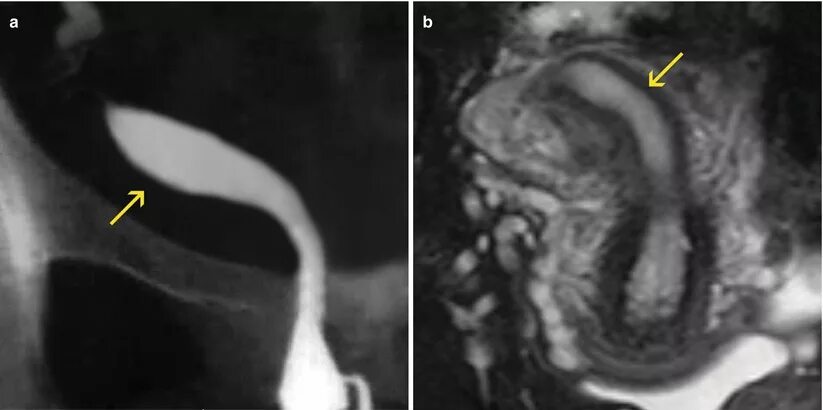

Аномалия полов орган